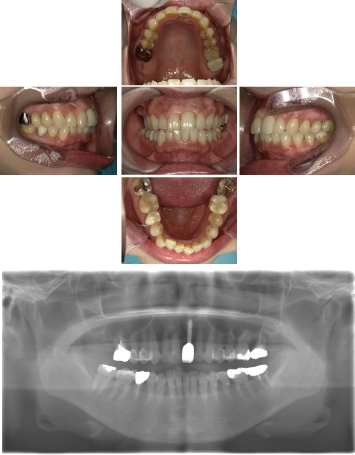

インプラント治療(左上5ソケット・GBR 右上2左上13GBR)

| 年代・性別 | 50代・男性 |

|---|---|

| 主訴 | 入れ歯だと咬めなくてつらい。 |

| 部位 | 上顎②1①2③4⑤Br |

| 治療期間 | 約9ヶ月 |

| 費用 | ¥1,794,100(税込) |

| 副作用・リスク |

|